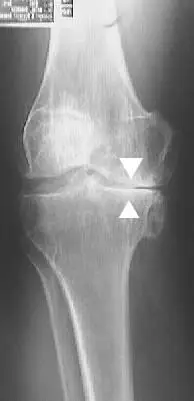

تشخيص خشونة الركبة بدقة

يعتمد التشخيص لدى دكتور هشام عبد الباقي على:

- الفحص الإكلينيكي الدقيق

- الأشعة السينية لتحديد درجة التآكل

- الرنين المغناطيسي لتقييم الغضروف والأنسجة المحيطة

التشخيص الدقيق هو حجر الأساس لاختيار علاج تآكل غضروف الركبة المناسب.

درجات خشونة الركبة

خشونة الركبة يمكن تقسيمها إلى عدة درجات بناءً على شدة الأعراض وتآكل الغضاريف، هذه الدرجات تساعد الأطباء في تحديد العلاج المناسب لكل حالة. إليكم تفصيل هذه الدرجات:

الدرجة الثانية

- زيادة الألم مع الحركة

- طقطقة في المفصل

- بداية ظهور نتوءات عظمية بالأشعة